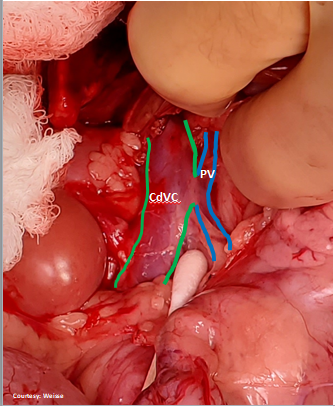

Does the MAIN Portal Vein (PV) DIRECTLY enter the Caudal Vena Cava (CdVC)?

WEISSE 2022

“PORTO-CAVAL (PC) SHUNT”